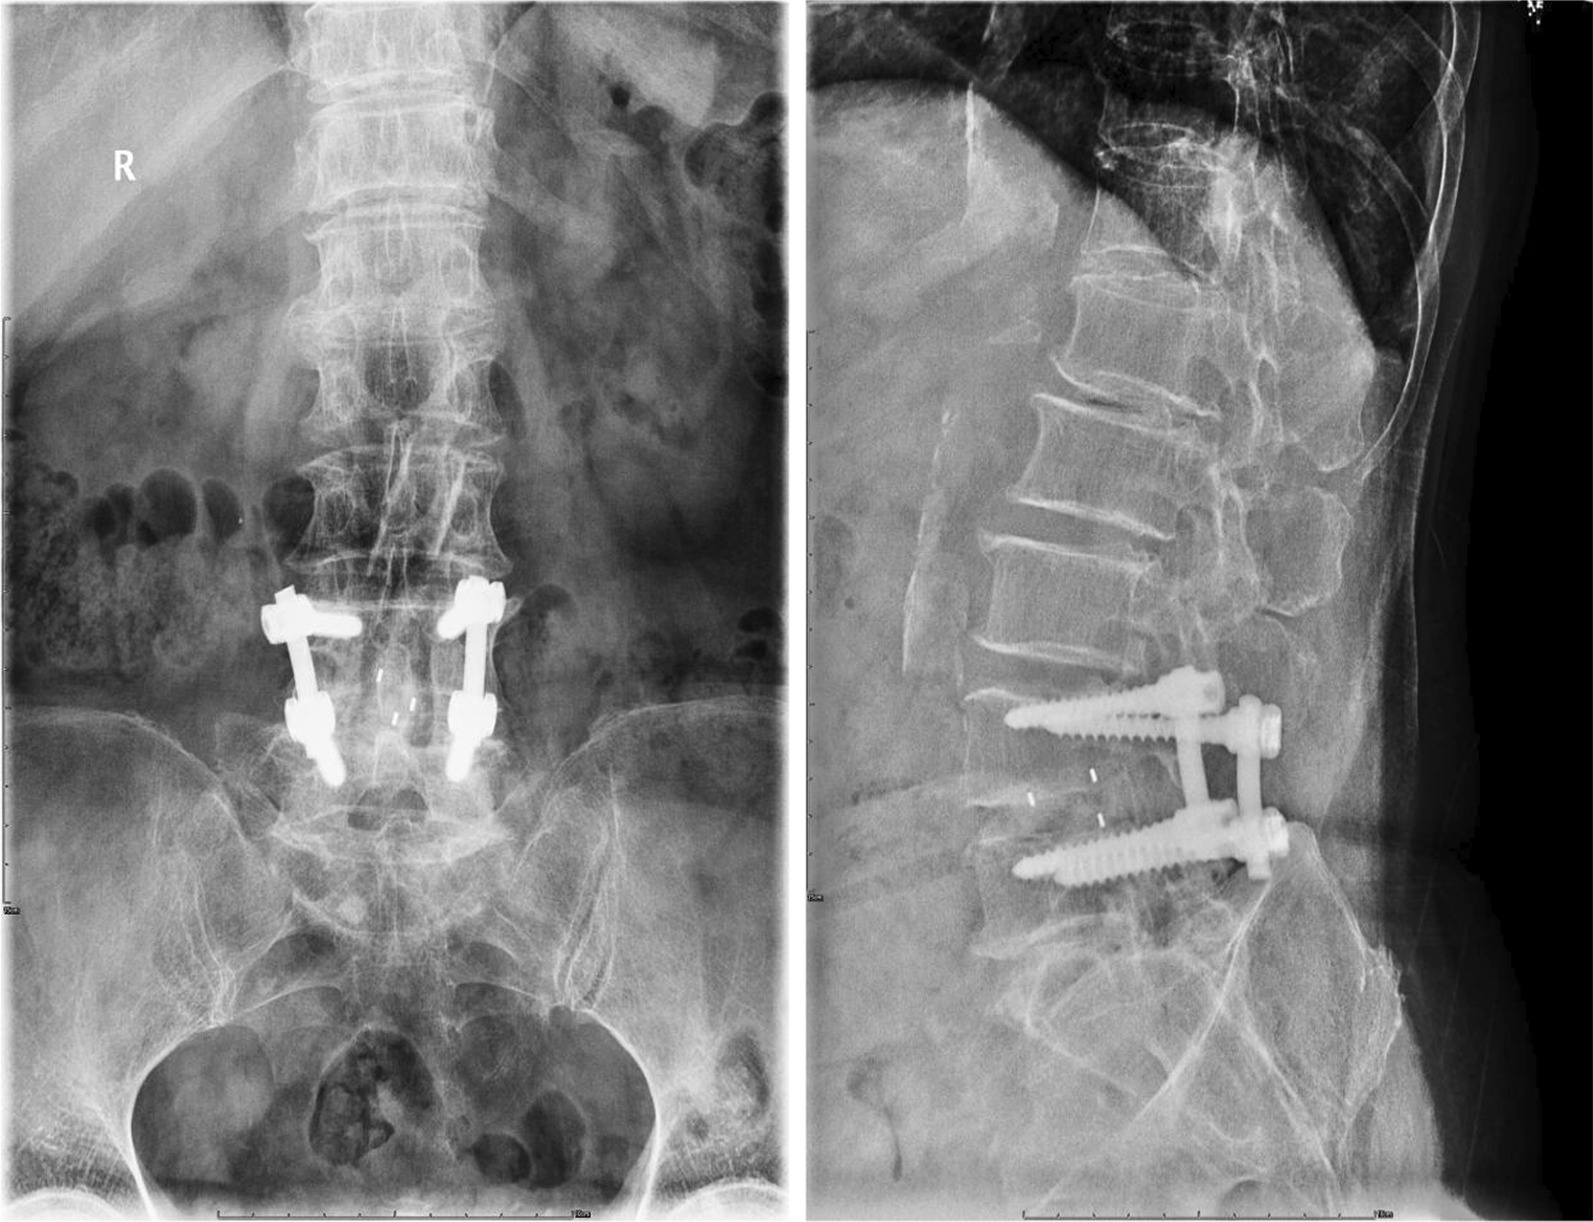

In determining fusion grades, each observer classified a case with three grades as definite fusion (grade I) (Fig. 5), non-union (III, IV), or probable fusion (II) (Fig. 6) using Bridwell’s fusion grading system [12]. A case with a definite finding was determined by the agreements of two observers. A case with a probable finding was determined by the agreement of two observers or by one observer’s decision of definite finding with another’s decision of probable (Fig. 7). The fusion rates with definite (86.7%) and probable (6.7%) grades in the BLIF group were higher than that in the ULIF group (definite: 70% and probable: 3.3%), with a statistically significant difference (P < 0.05) (Table 8). One case of cage subsidence with no screw loosening occurred in each group; thus, there was no obvious difference between the two groups (P > 0.05) (Table 9).

Fig. 5.

One of the “definite fusion” cases